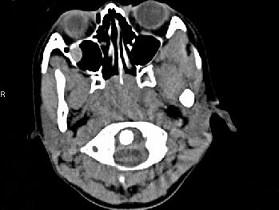

女,8岁,头痛,鼻塞半年余,CT如图所示,最可能诊断为 ( )A、神经纤维瘤B、咽后脓肿C、鼻咽部炎症D、腺样体肥大E、鼻咽癌

问题 女,8岁,头痛,鼻塞半年余,CT如图所示,最可能诊断为 ( )

选项 A、神经纤维瘤 B、咽后脓肿 C、鼻咽部炎症 D、腺样体肥大 E、鼻咽癌

答案 D